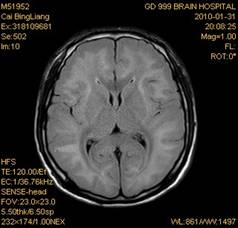

案例2 患者,女,30岁,二氯乙烷中毒性脑病的头颅MR。表现为双侧大脑半球皮层下白质、双侧外囊、双侧苍白球及双侧小脑齿状核内广泛片状、斑片状长T1长T2异常信号影,FLAIR序列呈高信号,增强后病变未见明显强化。

给予抗炎、脱水、疏通血管及营养神经等药物治疗。经过40天的对症治疗,痊愈出院。